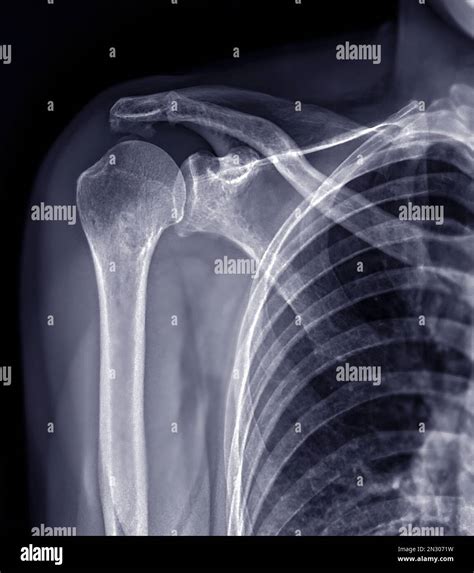

The shoulder joint is a ball-and-socket joint composed of three main bones: the humerus (upper arm bone), the scapula (shoulder blade), and the clavicle (collarbone). The joint is stabilized by a network of muscles, tendons, and ligaments, which allow for a wide range of motion. Understanding the anatomy is essential for interpreting X Ray Shoulder Joint images accurately.

• Fractures: Breaks in the bones of the shoulder, such as the humerus, scapula, or clavicle.

• Dislocations: When the head of the humerus is forced out of the shoulder socket.

Interpreting X Ray Shoulder Joint results requires a trained eye. Radiologists look for specific signs and abnormalities that indicate various conditions. Some key points to consider include:

• Bone Density: Changes in bone density can indicate conditions like osteoporosis or bone tumors.

• Fractures: Visible breaks or cracks in the bones.

• Joint Space: The space between the bones can indicate the presence of arthritis or other degenerative conditions.

• Soft Tissue: Although X-rays primarily show bones, they can also reveal certain soft tissue abnormalities.

Radiologists use these findings to make a diagnosis and recommend appropriate treatment options.